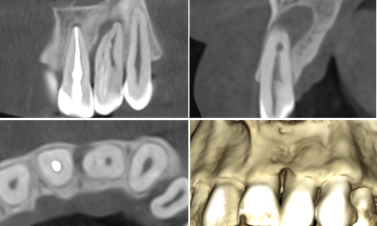

(фото 1) Холодова проба негативна.

Рентгендіагностика проводилась за допомогою апарата Veraview X800 Morita. На комп’ютерній томографії виявлено ділянку радіолюцентного просвітлення в периапікальній області, що має сполучення, з виявленою пародонтальною кишенею. Більше того, можна відмітити ділянки зуба за щільністю схожі на емаль. (фото 2)

Клінічний діагноз: інвагінація третього типа, некроз пульпи, асимптоматичний апікальний періодонтит. Прийнято рішення про ендодонтичне лікування. Оскільки, періапікальний дефект сполучається з порожниною рота за рахунок пародонтальної кишені, немає можливості досягти успіху лише застосовуючи терапевтичне лікування.